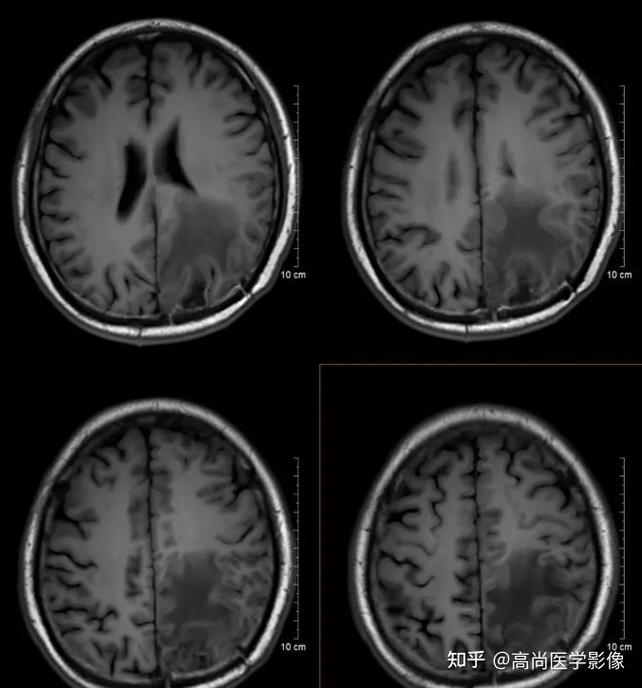

核心区别在于“密度”和“效应”,脑梗是“缺血缺氧导致的组织坏死”,而脑肿瘤是“异常增生的肿块”,我们可以从以下几个关键点来详细区分:

| CT平扫表现 | 低密度病灶 | 等/低/高密度均可,多为混杂密度 |

| 占位效应 | 早期不明显,随时间推移(3-5天后)逐渐出现 | 通常早期就有明显的占位效应(脑中线移位、脑室受压) |

| 病灶形态 | 楔形或扇形,符合血管分布区(如大脑中动脉区) | 圆形、类圆形或不规则,形态多样,边界可清或模糊 |

| 周围水肿 | 出现较晚(24-48小时后),范围相对局限 | 早期即可出现,范围通常比肿瘤本身大,呈“指压状” |

| 强化方式 | 一般不强化,或呈脑回状强化(提示侧支循环) | 多明显强化(均匀、不均匀、环形、花环状等) |

- 形态非常有特点:通常是楔形或扇形,其尖端朝向侧脑室,底边朝向大脑皮层,这是因为脑动脉供血区就是这种扇形分布。

- 位置:好发于大脑中动脉供血区(如基底节区、颞叶、顶叶)。

(图片来源网络,侵删)- 形态多样:多为圆形或类圆形,边界可清晰(如脑膜瘤)或模糊(如胶质瘤),位置没有特定规律,可发生在颅内任何部位。

- 水肿是继发性的,是脑组织对缺血坏死的反应,它出现得晚(通常在24小时后),且范围相对局限,主要围绕在梗死灶周围。

- 水肿是肿瘤本身特性(尤其是高级别胶质瘤和转移瘤),由肿瘤血管的异常通透性引起,它出现得早,且范围广泛,通常比肿瘤本身的体积还要大,呈“指压状”外观。